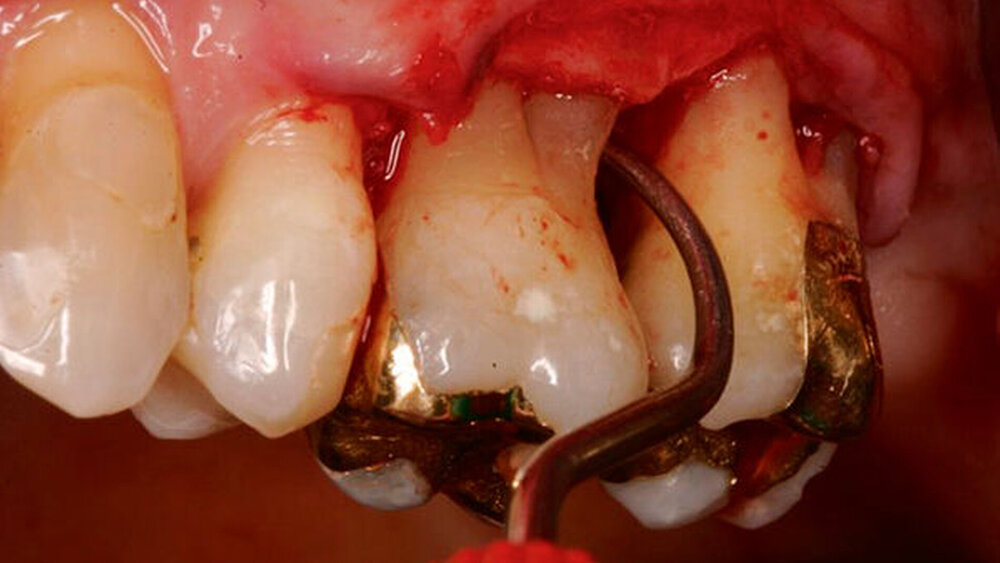

Werden verschiedene Zugangslappentechniken wie Instrumentierung unter Sicht mit Lappenbildung (Open Flap Debridement, OFD), Lappen mit paramarginaler Inzision (modified Widman Flap, MWF, Abbildungen 1 und 2), und Papillenerhaltungslappen (Abbildung 3) als konservative parodontalchirurgische Interventionen ohne signifikanten Weich- und Hartgewebsverlust hinsichtlich der Reduktion der TST verglichen, so bestehen kaum Unterschiede. MWF und OFD wurden in drei randomisierten klinischen Studien verglichen und nur eine davon hatte eine höhere Taschensondierungstiefenreduktion durch den MWF zum Ergebnis [Sanz-Sanchez et al., 2020].